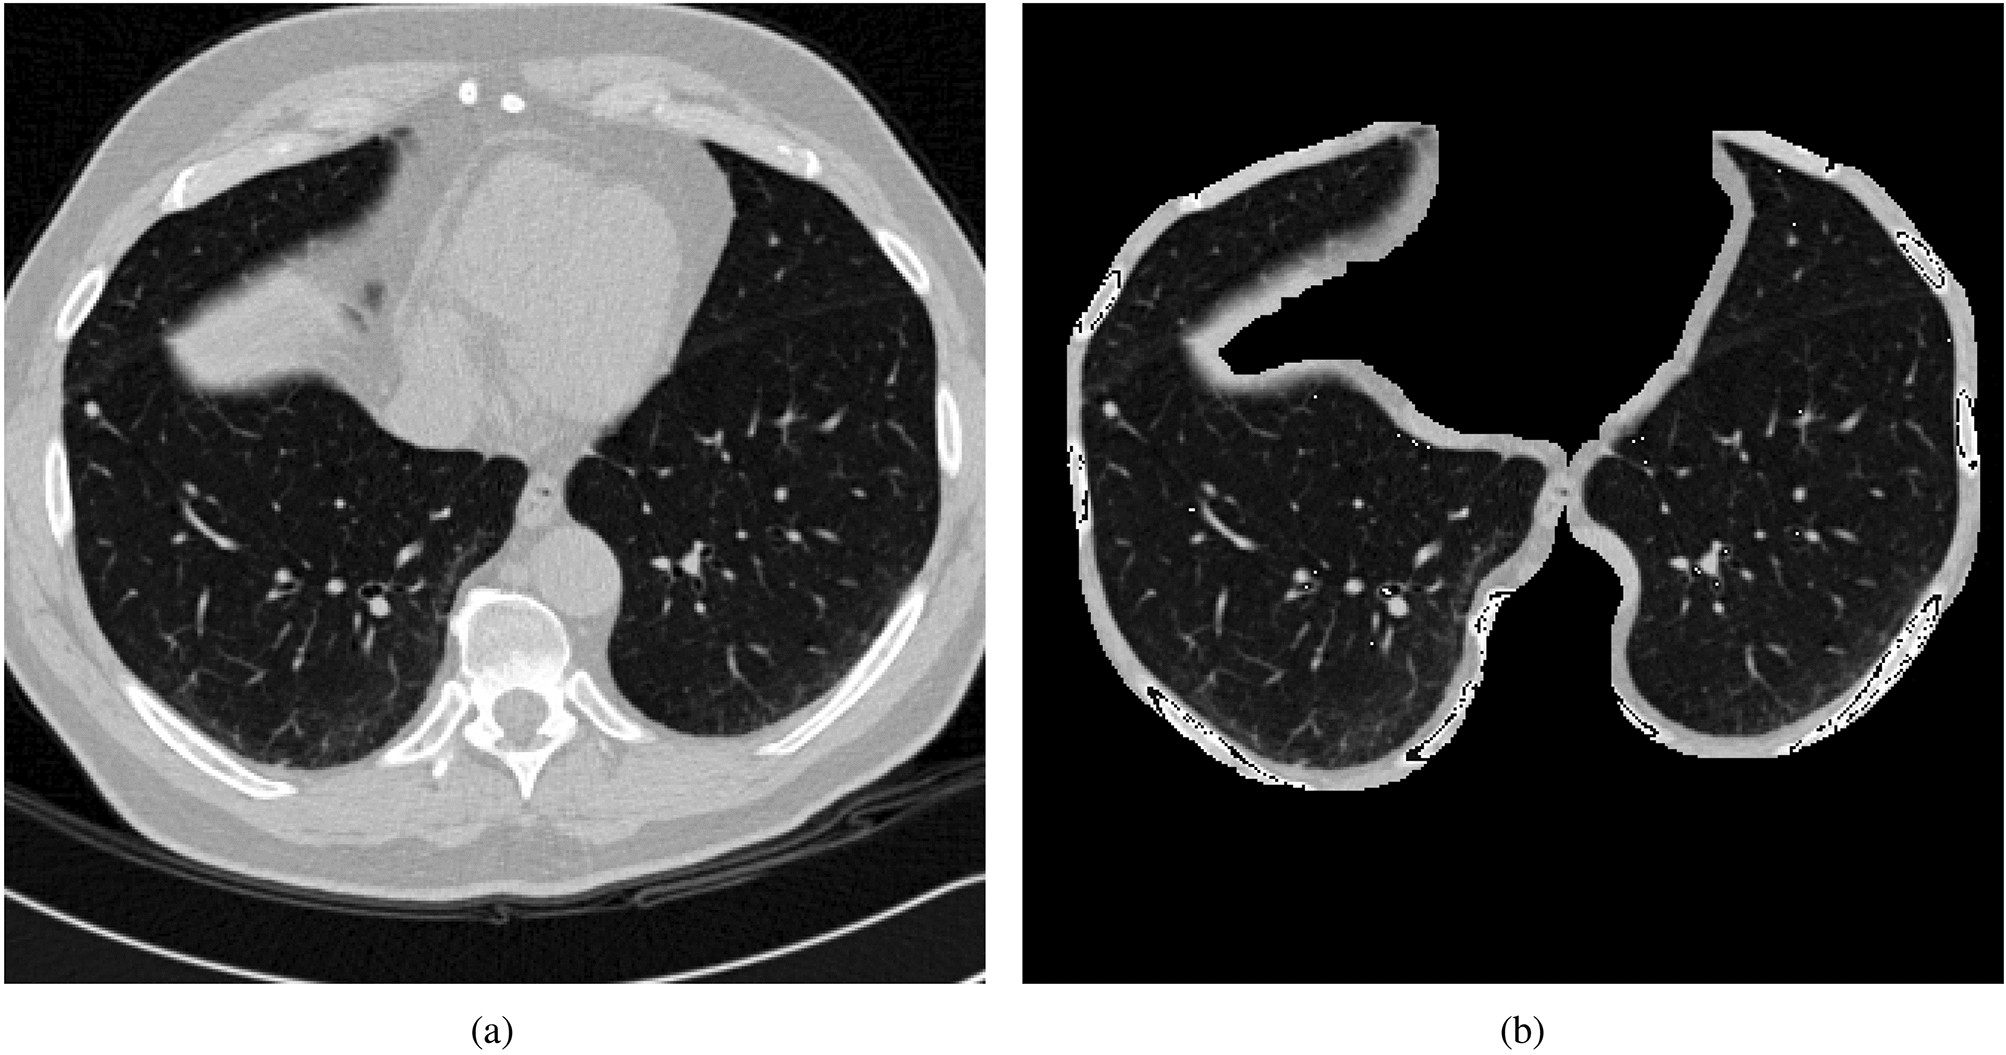

Original images and segmented images.